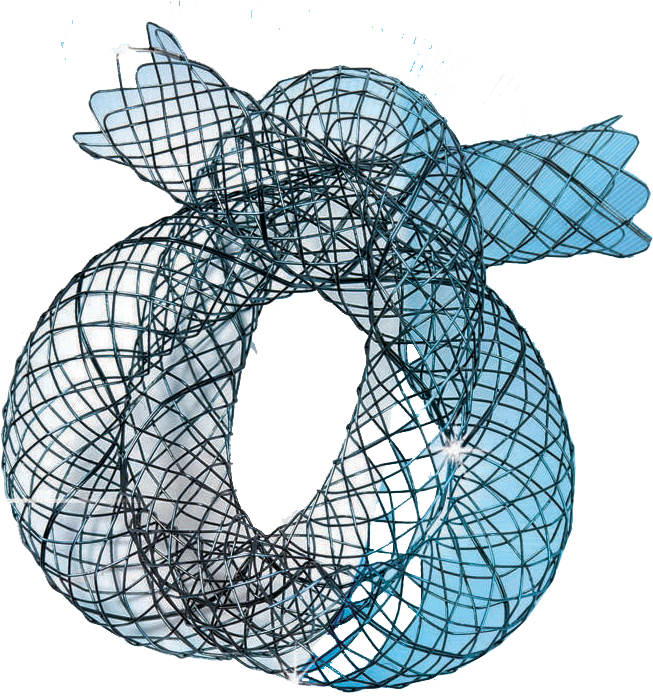

Thrombosis is a serious condition where one or more blood clots form in your blood vessels or heart. When this happens, the clot can block blood flow where it formed, or it can break loose and travel elsewhere in your body. If a moving clot gets stuck in a critical area, it can cause life-threatening conditions like stroke and heart attack.